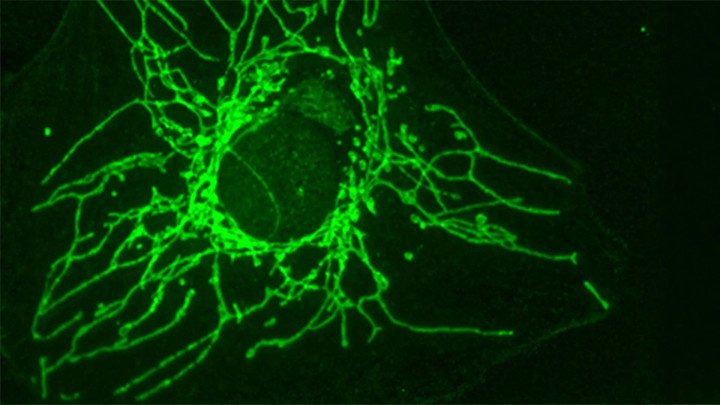

日内瓦大学分子与细胞生物学系名誉锤真金不怕火让-克劳德·马蒂努携带的团队,在系统筛选多种氨基酸对癌细胞孕育的影响时,发现了一个令东说念主奋斗的信号:D-半胱氨酸概况在现实室条目下显赫遏制某些癌细胞的增殖,而同等条目下的健康细胞却果然不受影响。

商榷发现,D-半胱氨酸通过一种特定的转运卵白参加细胞,而这种转运卵白只在某些癌细胞名义高度抒发,普通细胞上果然不存在。这相配于D-半胱氨酸手抓一张只须癌细胞才调识别的"入场券",幸运飞艇app下载健康细胞的大门对它耐久关闭,它也就无从参加、无从施害。

商榷论文第一作家、博士生约瑟芬·赞加里在解释这一机制时补充了一个要道的正向考据:当商榷东说念主员东说念主为地在健康细胞名义引入这种转运卵白,健康细胞便驱动招揽D-半胱氨酸,当场罢手增殖。这一现实平直讲授了"转运卵白的有无"是决定细胞红运的要道开关,而非细胞本人对D-半胱氨酸的内在耐受各异。